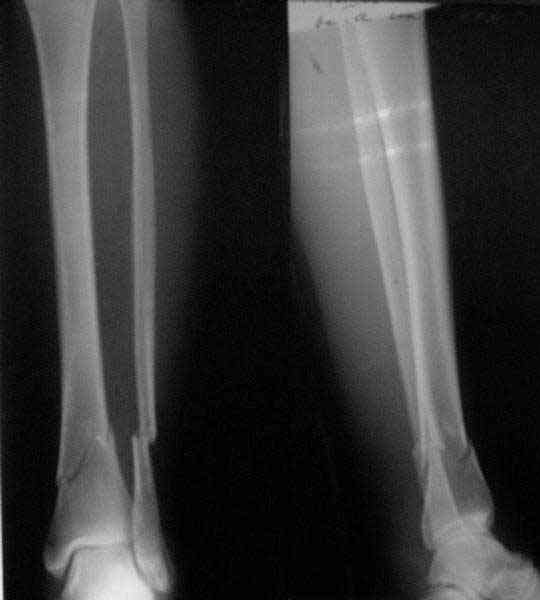

A typical case is attached, also an image with intra-op reduction obtained by a small wire distractor, in the moment of insertion a Poller wire in AP direction. Fixation by a SIGN nail. Despite the fibula was not fixed healing was obtained with the unchanged alignment.